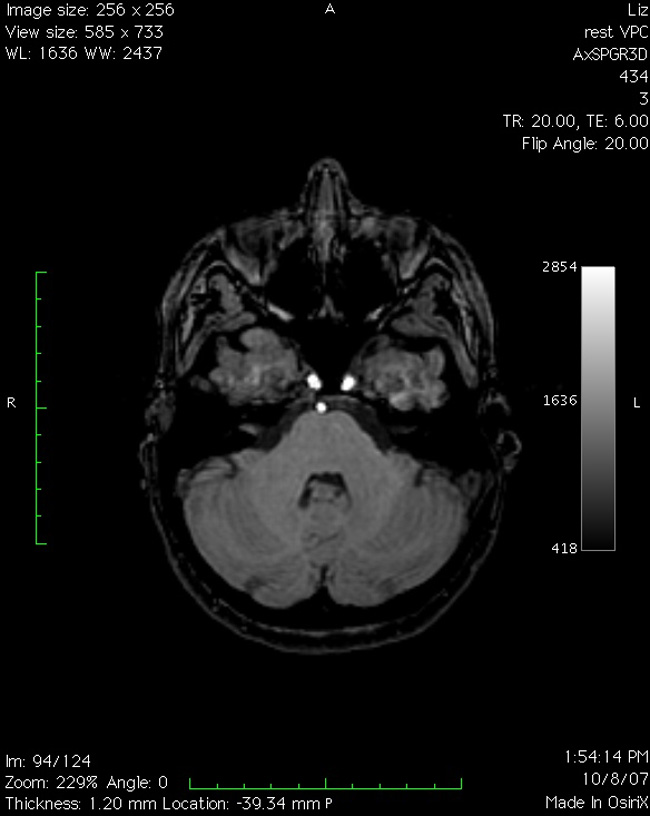

TERRENOS ESCANEADOS/fMRI on an Affordaplane surface

. Basement installation (entry from N.Hancock Street, Richmond, VA); initiated by a neuroimaging experiment. 2008.